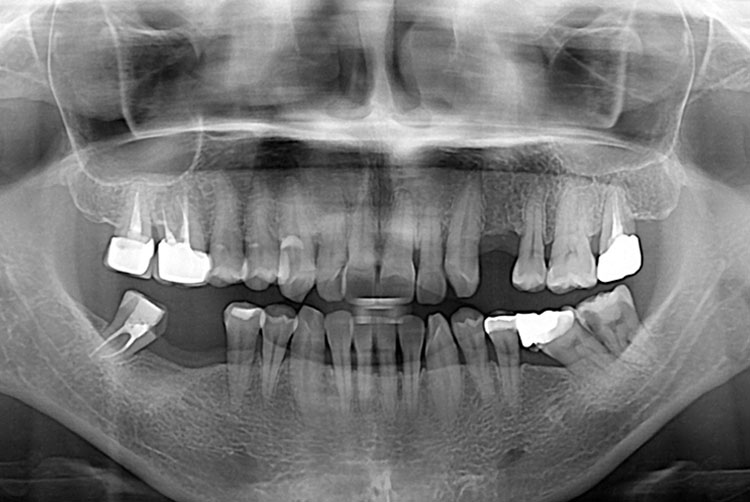

[임플란트] 임플란트

양경희_후.jpg

치료후 : 2016-11-30

세종치과는 많은 환자와 다양한 케이스를 바탕으로 항상 편안한 임플란트 수술을 제공하고자 노력하고,

오래동안 튼튼히 쓸 수 있는 임플란트 수술을 가장 큰 목표로 삼고 있습니다.